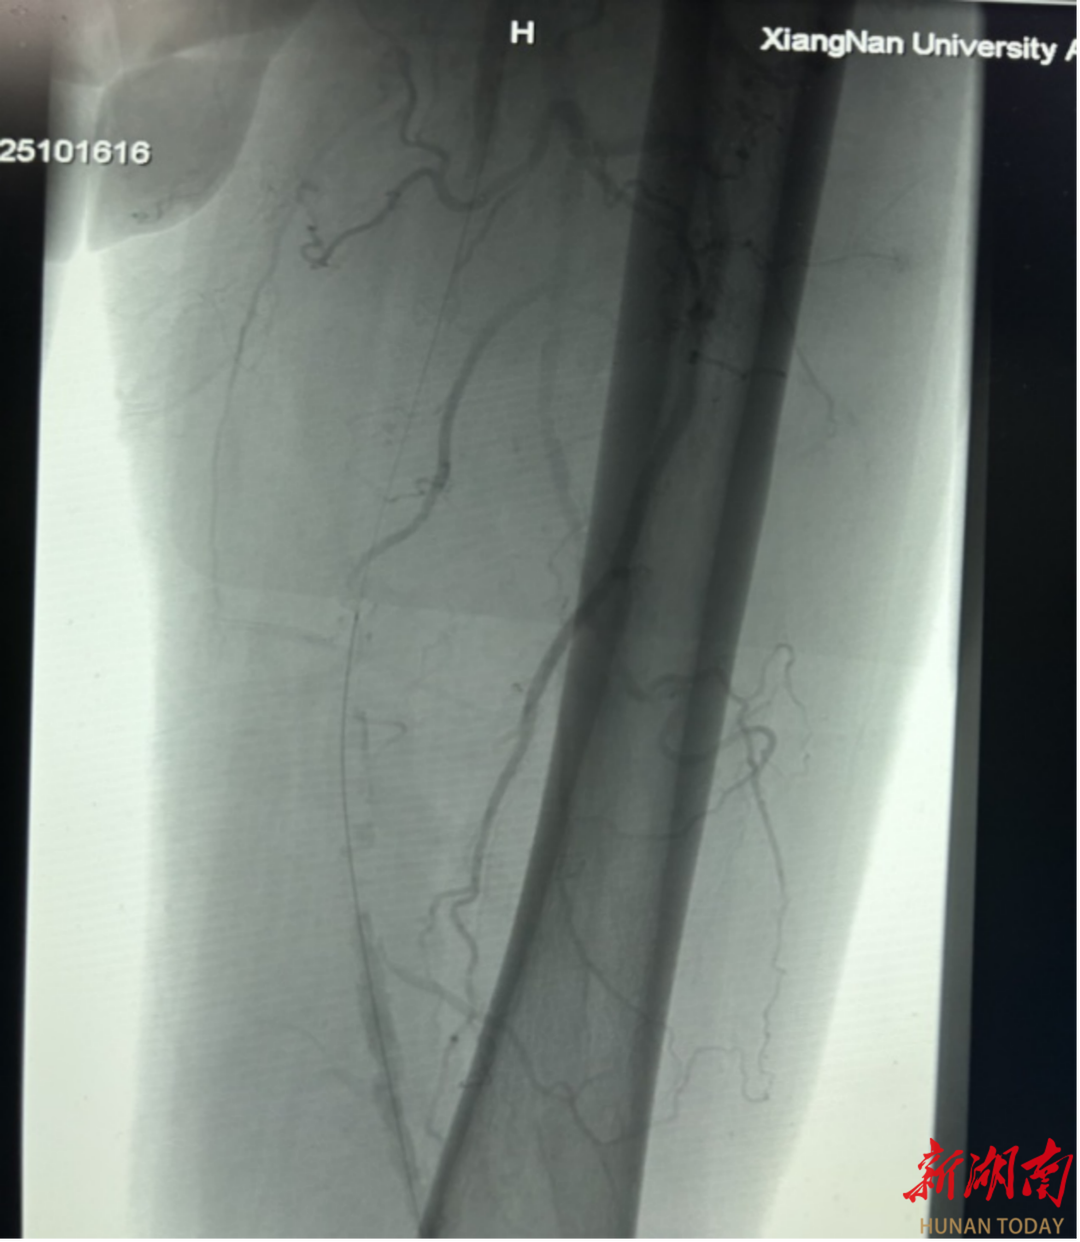

术前、术后造影对比图

手术当天,紧张的气氛弥漫在手术室。医生们通过股动脉穿刺,小心翼翼地将栓塞保护伞导入腘动脉,这一“保护伞”如同忠诚的卫士,准备兜住旋切过程中脱落的小斑块。在左股动脉中断,斑块旋切术正式开始。手术器械如同微型“刨子”,在直径仅几毫米的血管腔内辗转腾挪。医务人员凭借着精湛的技术,多次调整不同方向进行旋切刨吸。每一次切割都犹如在钢丝上行走,切得太薄无法达到治疗效果,切得太厚则可能损伤脆弱的血管。经过近两个小时的艰苦奋战,手术团队终于成功地将斑块切除并取出,随后药物球囊顺利扩张狭窄血管,抑制内膜增生,确保下肢动脉血流畅通。

术后立见成效,患者重获行走自由